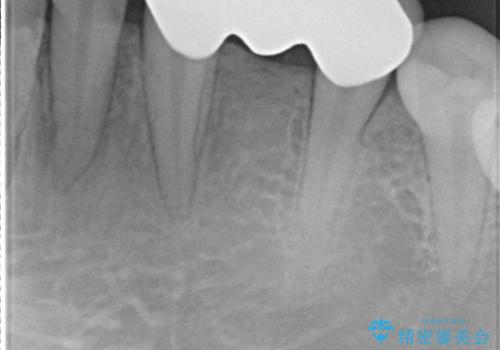

- 左下の歯が生まれつき無かった患者様です。

矯正治療にてスペースを一箇所に集めてからオールセラミックブリッジにて補綴治療を行いました。

今回は、患者様の希望もありインプラントではなくブリッジにて修復しています。